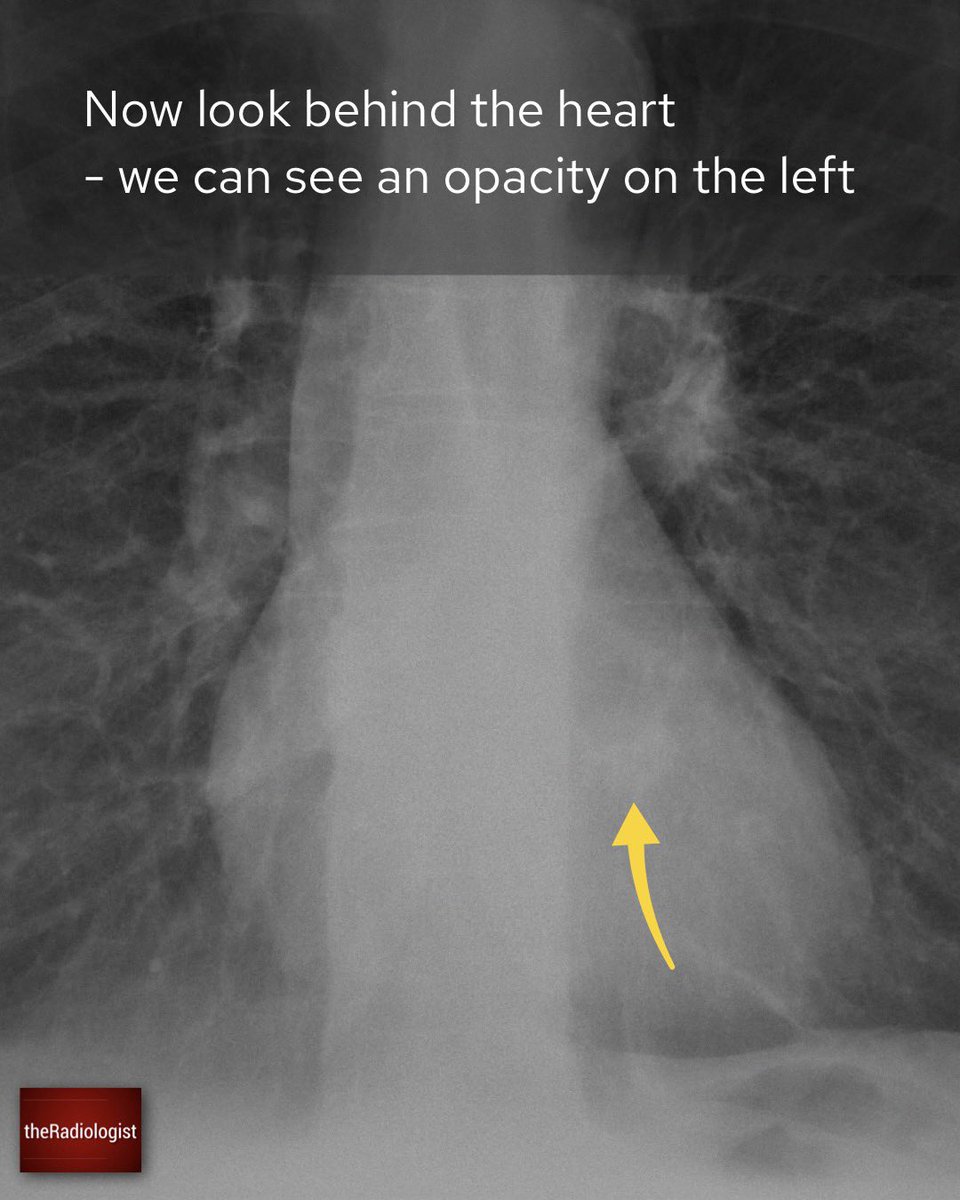

Explanation 2/3